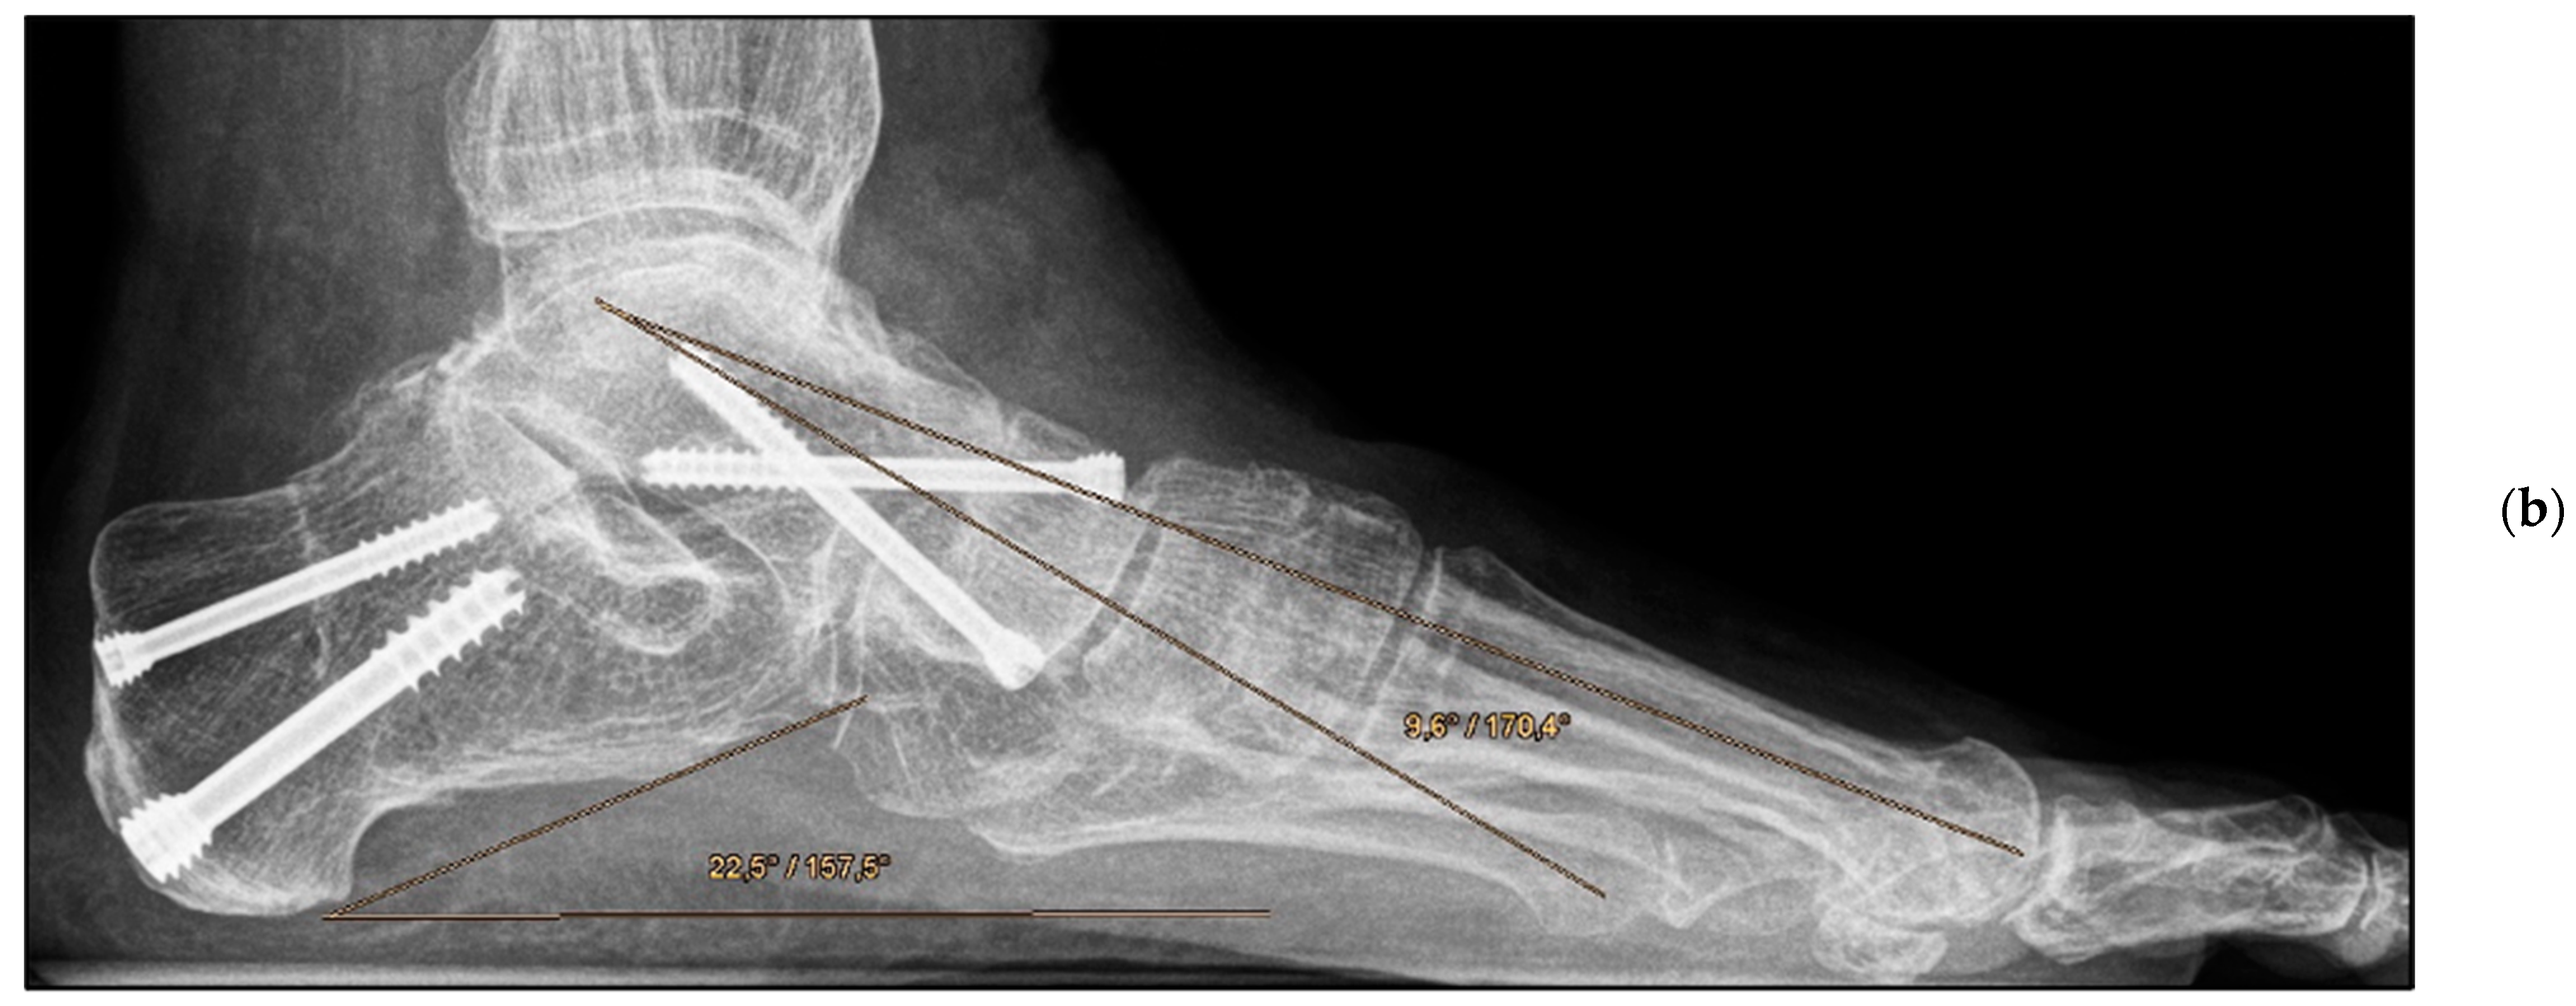

Figure 3.

Pre- and post-operative radiographic findings of combined talonavicular arthrodesis and calcaneal displacement osteotomy, left foot. (a) Lateral view pre-operative, (b) lateral view post-operative.

Medial calcaneal displacement osteotomy and talonavicular arthrodesis (Group A). In the first step, a V-shaped osteotomy was performed via an oblique approach to the lateral calcaneus with medial displacement of the back portion of the calcaneus. Osteotomy was performed using either an oscillating bone saw or bone chisel. Depending on the extent of the deformity, a medial displacement of approximately 8–10 mm was considered optimal. Fixation was achieved by means of two percutaneously inserted lag screws with diameters of 4.0–6.5 mm. The second step was talonavicular arthrodesis via a dorsal approach, usually with interposition of an iliac crest bone graft. Fixation was performed using two or three screws with diameters of 4 mm or a combination of screws and Nitinol compression implants (Figure 2a,b and Figure 3a,b).